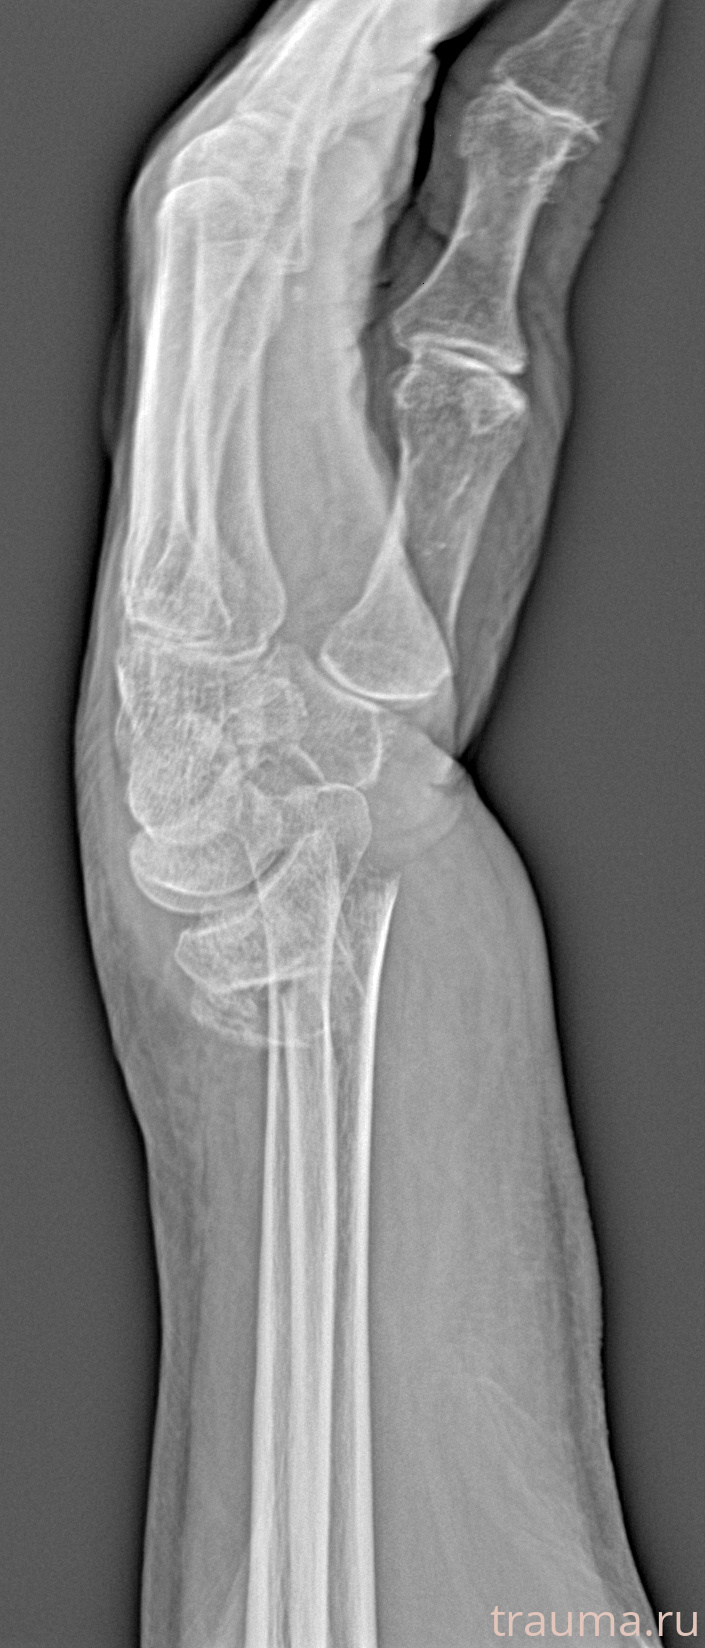

Рентгенограммы

Рентген на дому: по вашему адресу приезжает врач-рентгенолог, травматолог-ортопед с мобильным рентгеновским аппаратом, проводит диагностику травмы или заболевания, делает необходимые рентгенограммы, дает рекомендации по дальнейшему лечению. Получить качественные снимки в домашних условиях возможно благодаря уникальной методике, разработанной МосРентген Центром для института  Склифосовского